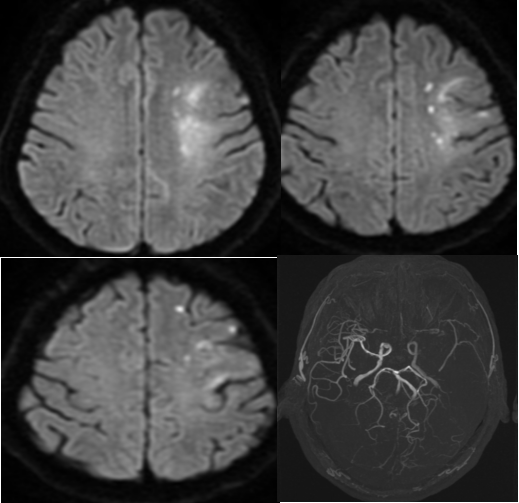

患者转回CCU监护生命体征平稳,但于下午约16:50出现嗜睡、失语、右侧肢体无力,请脑科中心二区刘添副主任医师急会诊,查看患者完全性失语,右侧肢体肌力0级,无恶心、呕吐,考虑急性缺血性脑卒中。急查颅脑核磁共振检查见:左颞叶、半卵圆中心、放射冠、岛叶多发急性梗死;磁共振血管造影见:左侧大脑中动脉闭塞、双侧大脑前动脉未显影,定位左侧大脑半球,责任血管为左侧大脑中动脉。综合检查,考虑患者大血管闭塞,静脉溶栓效果不佳,建议跨过溶栓,直接血管内取栓治疗。

▲MRI左侧大脑半球急性梗死,MRA左侧大脑中动脉闭塞,双侧大脑前动脉未显影